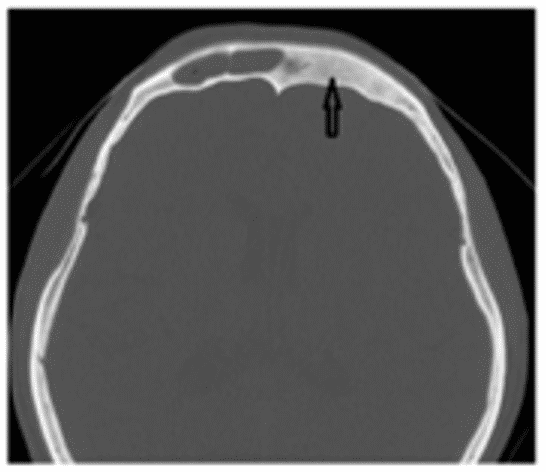

Остеобластома на КТ обычно представлена сочетанием плотной кости и участков затемнения (рисунок 4).

Рис. 4. КТ черепа, аксиальная плоскость. Гигантская остеобластома, распространяющаяся в правую орбиту, полость носа и переднюю черепную ямку

Данные КТ позволяют определить признаки локально агрессивного роста остебластомы, место ее исходного роста, наличие/отсутствие распространения опухоли за пределы околоносовых пазух.